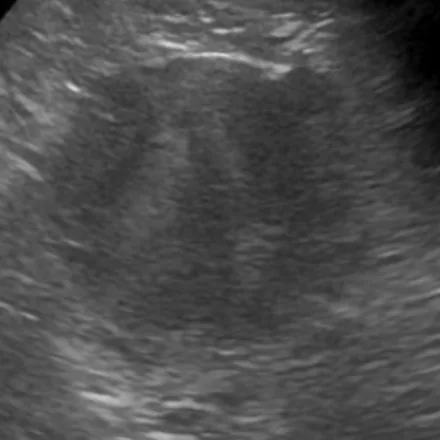

腹部超音波検査

副腎の評価(サイズや形)、血管との関連性を行います。